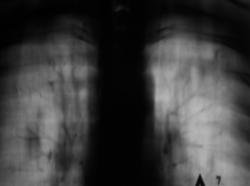

4._EGO..JPG